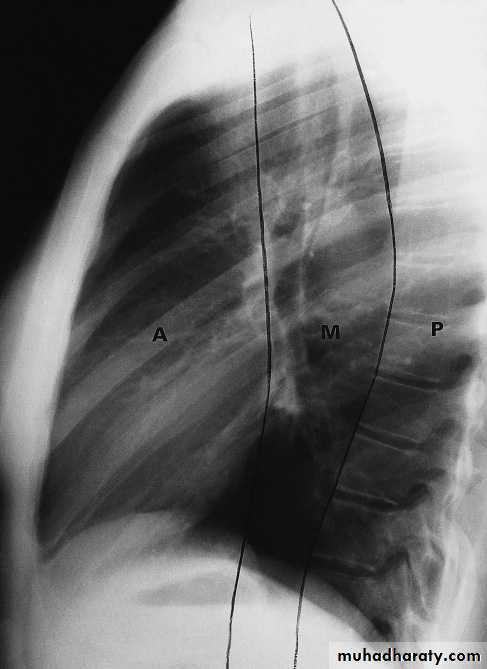

Frontal and lateral chest radiographs usually localize a mediastinal mass to a structure within the anterior, middle, or posterior mediastinal compartments. For instance, if the contours of a lesion are outlined by air and seen above the clavicles, then the lesion must be in the posterior mediastinum. Conversely, if the contours of a lesion are lost at the thoracic inlet level, it must be anterior

Posterior mediastinal lesions are seen on the lateral view projecting over the spine and are also paraspinous on the frontal chest x-ray. Most (90%) posterior mediastinal lesions are neurogenic.